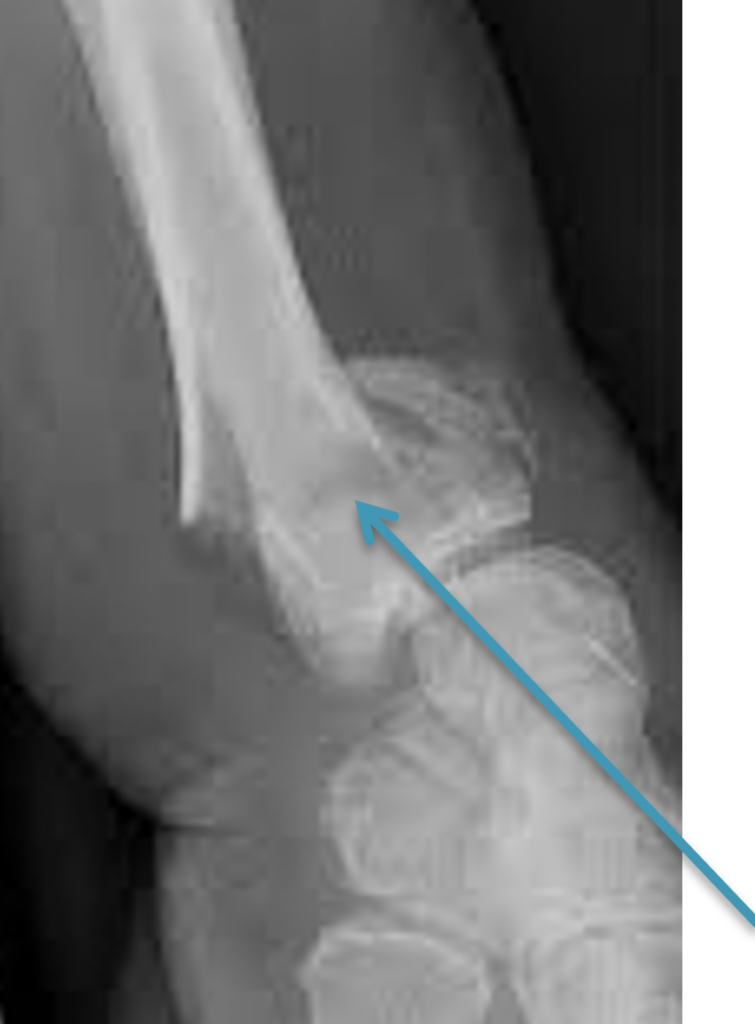

From www.alamyimages.fr

xray montrant une fracture de l'ulna et le radius Photo Stock Fracture Poignet Symptome  Douleur autour du poignet , la main et l'avant. Et quels traitements envisager ?. Toutes les définitions santé, symptômes et traitements sont sur docteurclic. Une douleur intense au niveau du poignet, qui peut irradier vers la main ou. Chute, accident de sport ou de travail. Les symptômes d’une fracture du poignet sont variables. Les symptômes d’une fracture du poignet sont. Fracture Poignet Symptome.